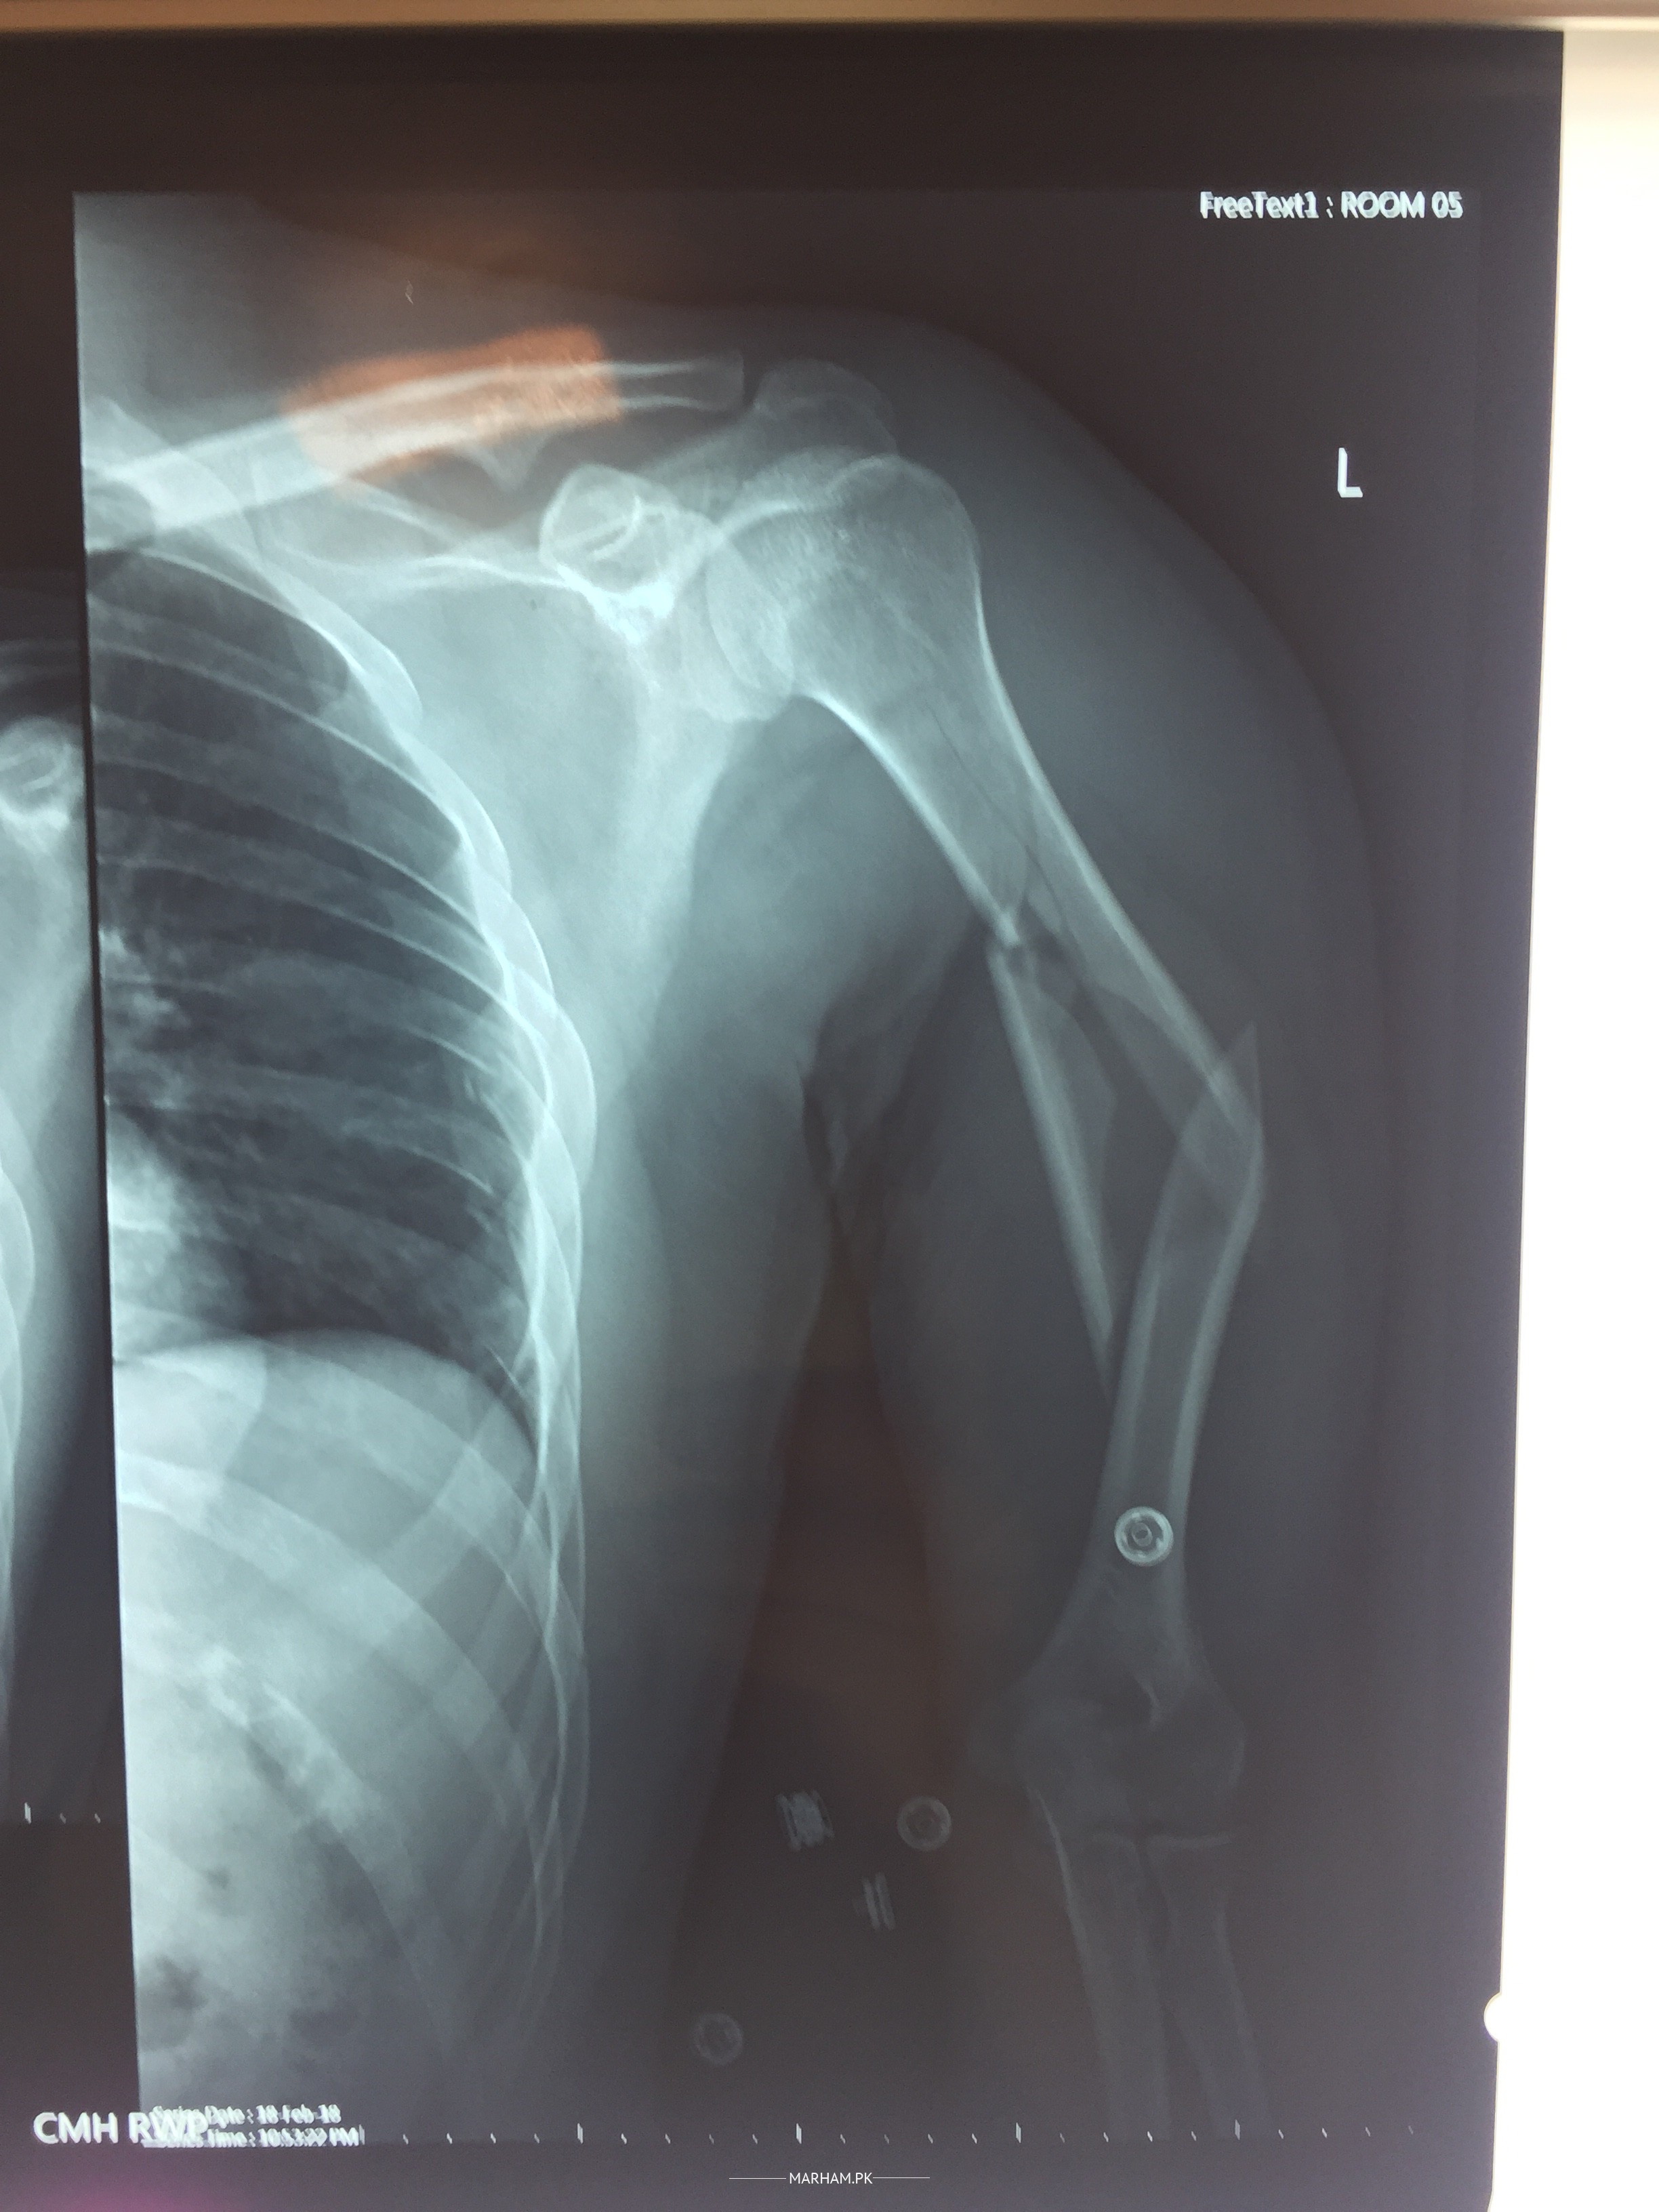

Attached are the pre surgery and post surgery X-ray images. is every thing fine

xrays are looking fine.